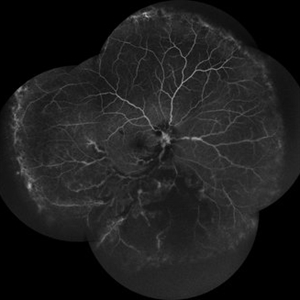

RPE rip in a case of Idiopathic polypoidal choroidopathy RPE rip in a case of Idiopathic polypoidal choroidopathyOct 23 2022 by Anjana Mirajkar, MS Ophthalmology Montage of Fluorescein angiography in a of 61 year old male with RPE rip in a case of Idiopathic Polypoidal Choroidopathy. Photographer: Dr. Anjana Mirajkar -Retina Foundation, Ahmedabad Condition/keywords: Idiopathic polypoidal choroidopathy, RPE rip